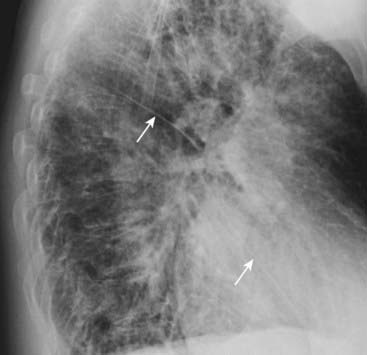

image When a fissure contains fluid or develops fibrosis from a chronic process, it will become thickened (Fig. 2-7).

Thickening of the fissure by fluid is almost always associated with other signs of fluid in the chest such as Kerley B lines and pleural effusions (see Chapter 6).

Thickening of the fissure by fibrosis is the more likely cause if there are no other signs of fluid in the chest.

image

Figure 2-7 Fluid in the major fissures.

Left lateral view of the chest shows thickening of both the right and left major fissures (solid white arrows). This patient was in congestive heart failure and this thickening represents fluid in the fissures. Normally, the fissures are either invisible or, if visible, they are fine, white lines of uniform thickness no larger than a line made with the point of a sharpened pencil. The major or oblique fissure runs from the level of the 5th thoracic vertebral body to a point on the anterior diaphragm about 2 cm behind the sternum. Notice the increased interstitial markings that are visible throughout the lungs and are due to fluid in the interstitium of the lung.